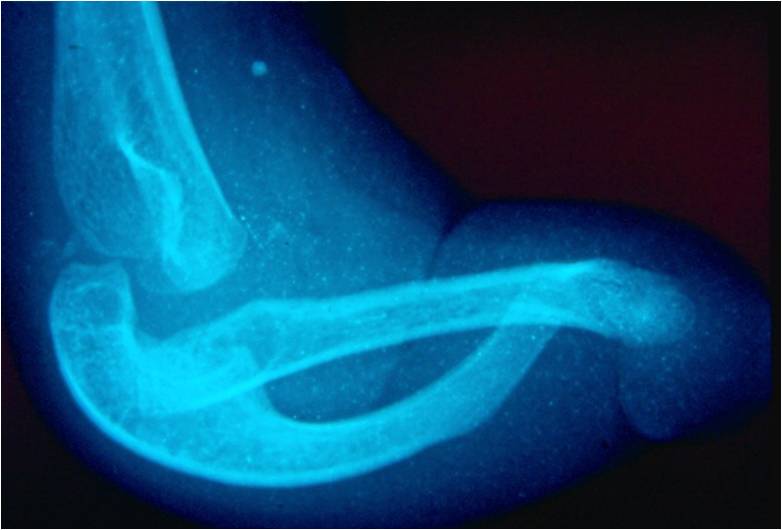

The radiographic follow-up evaluation showed pseudarthrosis of the ulna at its middle third and a tapering end of the proximal third, while the distal third presented as a thin intermittent sclerotic line with a residual distal meta/diaphysis and epiphysis. Marked bowing of the radius with proximal migration of the dislocated radial head was also evident. The final diagnosis was isolated congenital bowing-pseudarthrosis of the ulna with resorption of the middle diaphyseal third due to osteolysis in a patient with NF1 (Figure 6).

Figure 6. Congenital angulation-pseudarthrosis of the ulna with osteolysis in a boy with neurofibromatosis type 1. The radiographs were taken when the boy was 3 years old and the photographs when he was 9 years old.